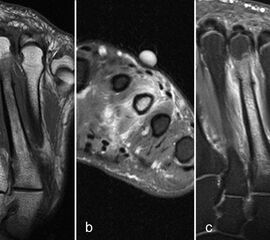

Der Begriff Morton-„Neurom“ ist im Grunde veraltet und irreführend, denn es handelt sich weder um einen Nerven- noch um einen Nervenscheidentumor, sondern um eine perineurale Fibrosierung. Da das interdigitale Gefäßnervenbündel charakteristisch in die Läsion hinein- und distal auch wieder aus der Läsion herauszieht, entsteht lediglich das Bild eines vom Nerven ausgehenden Tumors. Die charakteristischen Merkmale von Morton-„Neuromen“ sind deren Lage plantar auf Höhe der Metatarsaleköpfchen und die oft typische tropfenförmige Konfiguration (Abb. 10).

Aufgrund des hohen Bindegewebsanteils sind sie in der MRT in T2-gewichteten Bildern in der Regel auffallend signalarm, die T1 zeigt eine unspezifische Weichteilintensität. Die Anreicherung nach intravenöser Kontrastmittelgabe ist sehr variabel und erlaubt somit kaum diagnostische Rückschlüsse.

Durch seitliche Kompression des Fußes verlagern sich Morton-„Neurome“ oft weiter nach plantar in die Weichteile. Klinisch entspricht dies dem sogenannten Mulder-Zeichen 4. In der Bildgebung kann man sich den Effekt zu Nutzen machen, indem man in Bauchlage untersucht und durch die seitliche Fixierung eine entsprechende Kompression erzeugt. Die Befunde sind dann oft deutlich besser zu erkennen (Abb. 11).

Morton-„Neurome“ liegen fast immer im zweiten oder dritten Interdigitalraum. Zu beachten ist, dass Morton-„Neurome“ über lange Zeit größenkonstant sein können (Abb. 12) und kleinere Morton-„Neurome“ (unter 5 mm) sehr häufig bei asymptomatischen Gesunden beobachtet werden.